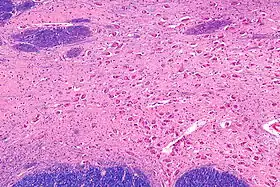

![]() صورة مجهرية متوسطة التكبير للنواة القاعدية. لطخة LFB-HE صورة مجهرية متوسطة التكبير للنواة القاعدية. لطخة LFB-HE | |